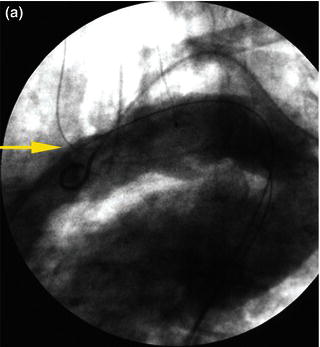

In tortuous aorta, the use of the brachio-femo ral wire may be required to aid advancement and deployment of an endograft. Deployment of an endoluminal graft in a tortuous aorta may be difficult, requiring the use of a brachio-femoral wire (Fig. 1.2). Use of brachio-femoral access wires can help straighten the most angulated of vessels. The presence of a tortuous aorta requires brachio-femoral access to deploy an endoluminal graft (Fig. 1.3). Brachial access is obtained by a percutaneous retrograde puncture of the right brachial artery with an 18 gauge needle or a micropuncture needle. An extra long 450 cm, 0.035 inch angled glide wire is advanced through the brachial sheath into the tortuous thoracic aorta, snared and pulled out through the groin sheath. The technique requires that a protective guiding catheter be placed over the brachial artery to protect the subclavian artery from injury. It is important to have at least a 260 cm long wire and constant tension must be placed on both ends of the wire as the delivery sheath is passed into the aorta [2,3]. By pulling on both ends of the wire an endoluminal graft can be advanced up into the tortuous arch aorta with precise deployment of the endoluminal graft.

Fig. 1.2 (a) Angiogram and (b) illustration demonstrating advancement of a brachio-femoral wire in a tortuous thoracic aorta.

Fig. 1.3 (a) Angiogram and (b) illustration demonstration of deployment of a thoracic endograft using a brachio-femoral wire approach.